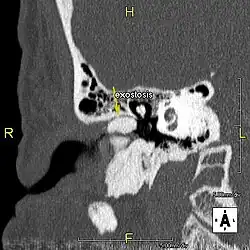

Exostose du surfeur

L'exostose du surfeur ou oreille de surfeur est une exostose, c'est-à-dire une croissance osseuse anormale, qui pousse vers l'intérieur du conduit auditif[1]. L'os entourant le conduit auditif réagit à l'agression thermique et mécanique de l'eau froide et de ses turbulences, par une nouvelle croissance osseuse qui a pour effet de resserrer le conduit auditif.

Du fait de la réduction du diamètre du conduit auditif, l'eau et le cérumen peuvent rester piégés entre la masse osseuse et le tympan et provoquer ainsi une infection comme une otite externe, particulièrement douloureuse.